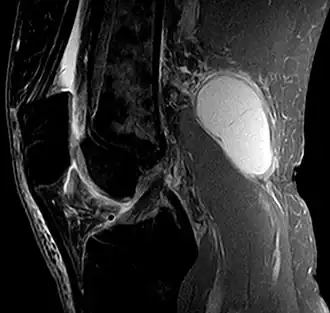

![]() Quiste de Baker, en una imagen sagital obtenida por resonancia magnética. | ||

El quiste de Baker (también, quiste común o quiste poplíteo) es una formación de contenido sinovial producida al debilitarse la membrana sinovial que recubre la articulación de la rodilla. Este líquido sinovial se acumula en la bolsa del gastrocnemio-semimembranosa que se comunica con la articulación de la rodilla a través de una abertura en la superficie posterior y medial de la cápsula articular.[2][3] El quiste de Baker puede aparecer a cualquier edad, incluso en las primeras etapas de la vida. La ruptura de un quiste de Baker origina un cuadro generalmente agudo que se acompaña de tumefacción y dolor del miembro inferior afectado que lleva a impotencia funcional. Muchas veces es confundido con la trombosis venosa profunda por su similitud clínica.[4]